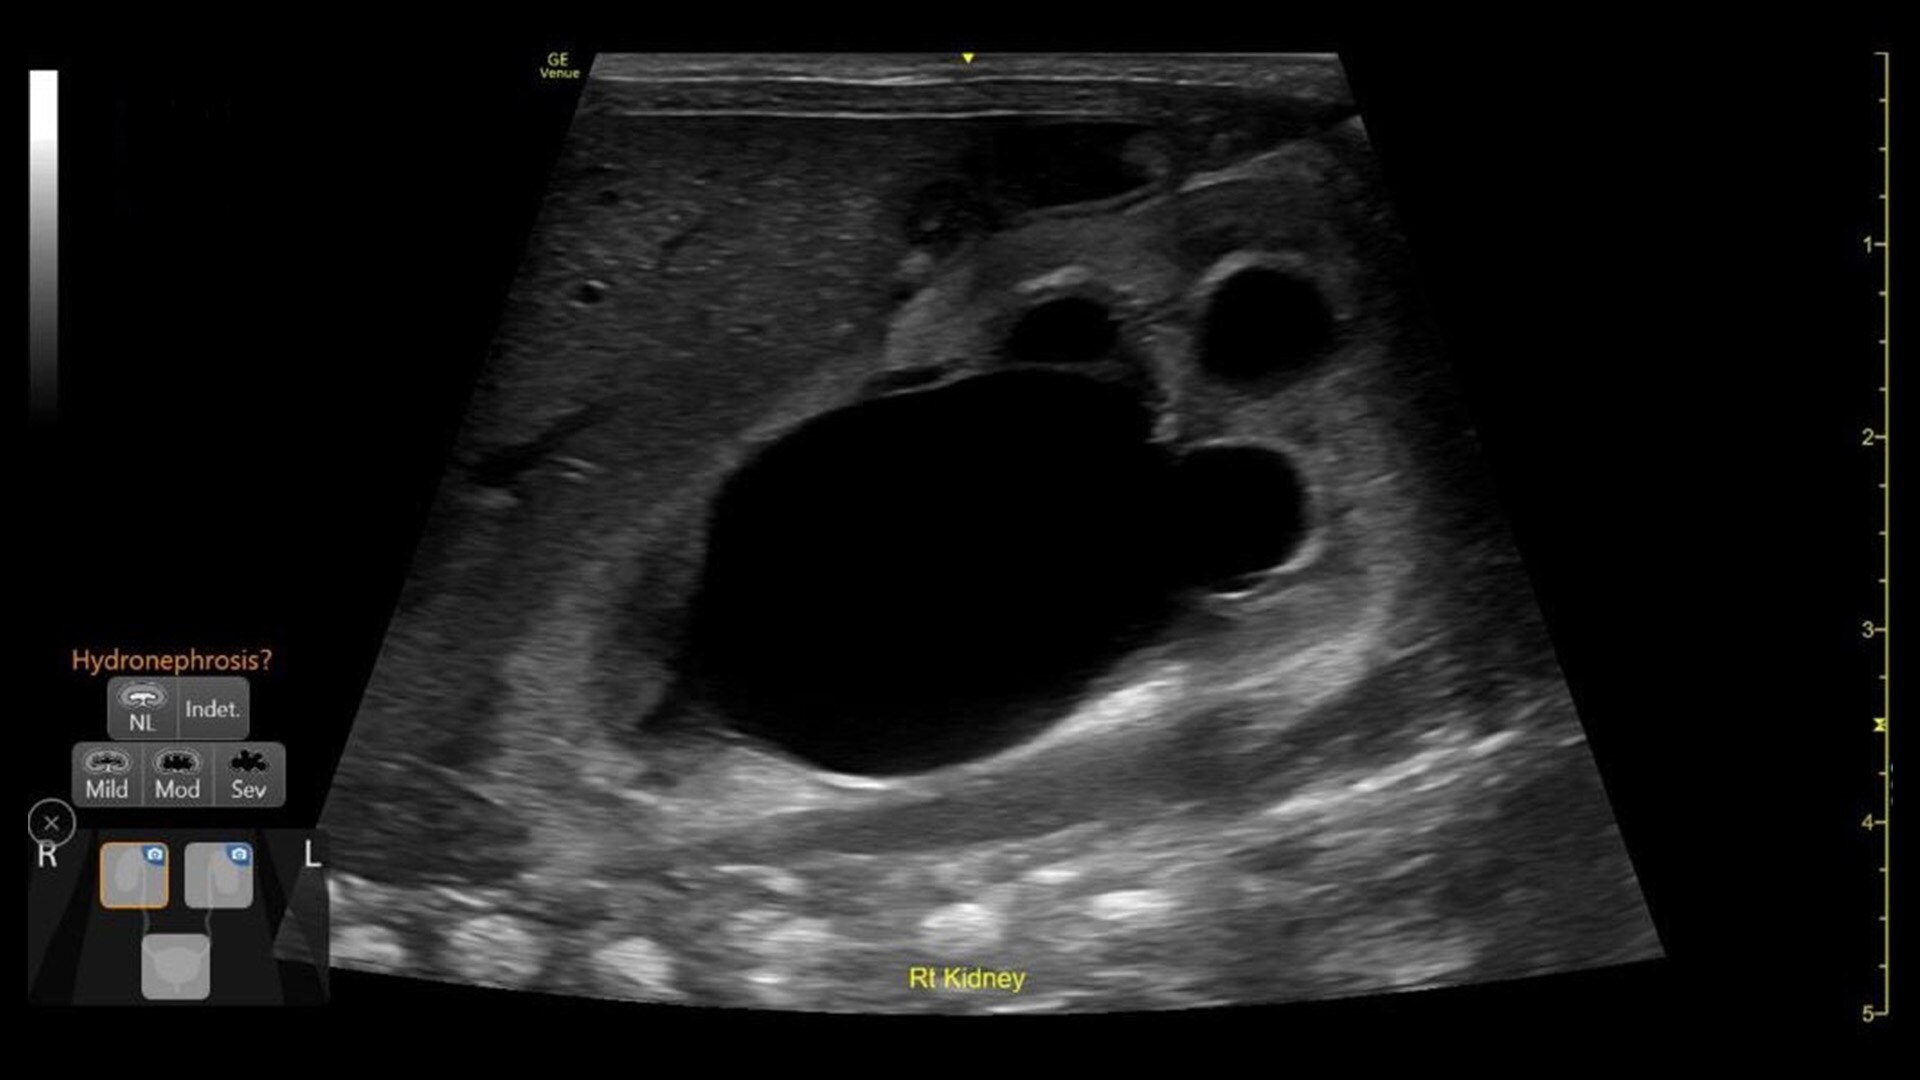

Quickly assess kidneys and the bladder with Renal Diagram

Simplify documentation and provide easy follow up for patients with suspected hydronephrosis. No need to type findings; simply assign a label from a pre-populated list that correlates with images.

renal-diagram-review-desktop